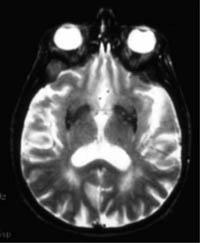

She remained symptom free for 18 months, after which she suffered a full recurrence. A follow-up magnetic resonance imaging (MRI) scan showed new compression of the non-treated right cerebral penduncle by the opposite posterior cerebral artery.

Based on this case, Jannetta and his AGH colleagues conducted a blinded MRI study analyzing the brains of 20 patients with Parkinson's and 20 healthy control subjects. The study showed 78 percent of the Parkinson's patients had visible arterial compression/distortion of one or both cerebral penduncles.

Of the study's 20 control subjects, just two had low-grade compression of the cerebral penduncle and one of those was subsequently diagnosed with Parkinson's.